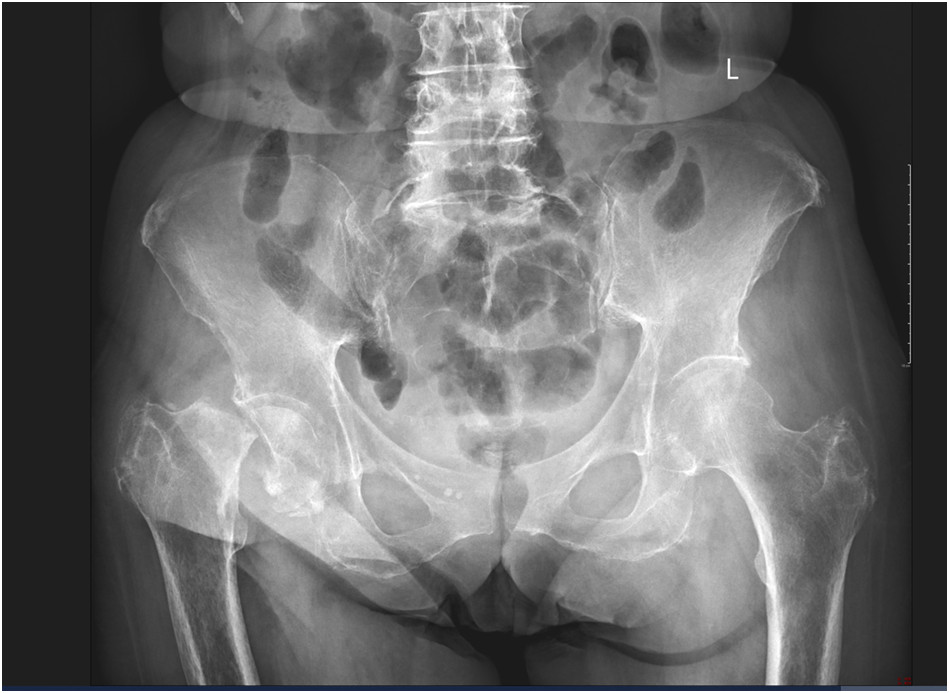

75-letnia chora została przywieziona przez zespół ratownictwa medycznego do Szpitalnego Oddziału Ratunkowego. Lekarz dyżurny zlecił wykonanie radiogramu (poniżej) oraz konsultację specjalisty w dziedzinie ortopedii i traumatologii narządu ruchu.

W wywiadzie i badaniu przedmiotowym u chorej można stwierdzić z dużym prawdopodobieństwem:

1) przebyty uraz niskoenergetyczny, np. upadek z własnej wysokości;

2) ustawienie prawej kończyny dolnej w rotacji zewnętrznej;

3) ograniczenie bólowe zakresu ruchów w prawym stawie biodrowym;

4) skrócenie długości względnej prawej kończyny dolnej;

5) skrócenie długości bezwzględnej prawej kończyny dolnej.

Prawidłowa odpowiedź to: